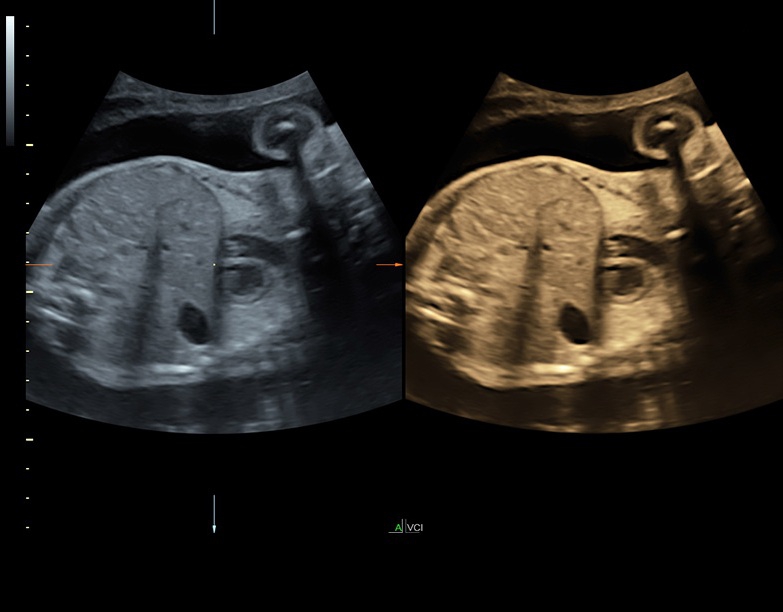

• Технология SonoRenderlive: Эта технология облегчает получение 3D/4D изображений путем автоматического изменения положения плоскости визуализации в зависимости от движений плода. Она позволяет получить реалистичные и объемные изображения, что полезно для демонстрации плода будущим родителям и для дополнительного анализа.

• Расширенный программный пакет объемного контрастного изображения (VCI) для объемных датчиков